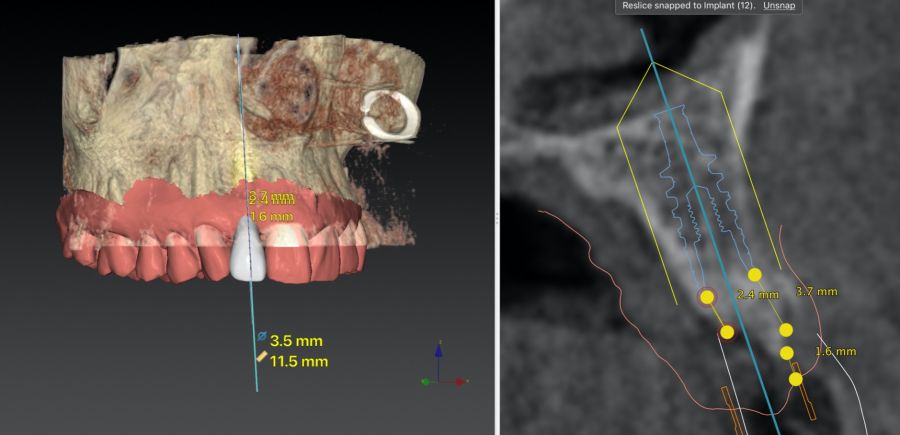

-Fase II: la cicatrización transcurrió sin complicaciones. Tras 5 meses de la cirugía de preservación alveolar, se planificó la cirugía implantológica guiada en posición 1.2 (Figura 2). Para ello, se utilizaron un archivo DICOM procedente de la tomografía computarizada de haz cónico (CBCT) y el archivo STL procedente del escaneado mediante un escáner óptico intraoral. Con esta información se construyó una férula quirúrgica de soporte dental (Figura 3). La férula quirúrgica se ancló sobre los dientes y guió la realización del lecho implantario y la colocación del implante. La técnica quirúrgica de cirugía guiada consistió en una cirugía con colgajo, preparando e insertando el implante (3,5 x 11,5 mm) según el protocolo estandarizado de cirugía guiada Nobel Active® (Nobel Biocare AB, Gothenburg, Sweden). Una vez colocado el implante 1.2, se obtuvo un injerto gingival compuesto de epitelio y tejido conectivo de la mucosa masticatoria palatina. A continuación, se realizó la desepitelización de la capa superficial de dicho injerto fuera de boca mediante una hoja de bisturí 15C con la finalidad de obtener un injerto de tejido conectivo de la capa subyacente18.

El injerto desepitelizado se insertó y posicionó por vestibular y oclusal mediante un punto colchonero horizontales utilizando sutura 5-0 no reabsorbible (Figura 4)19.